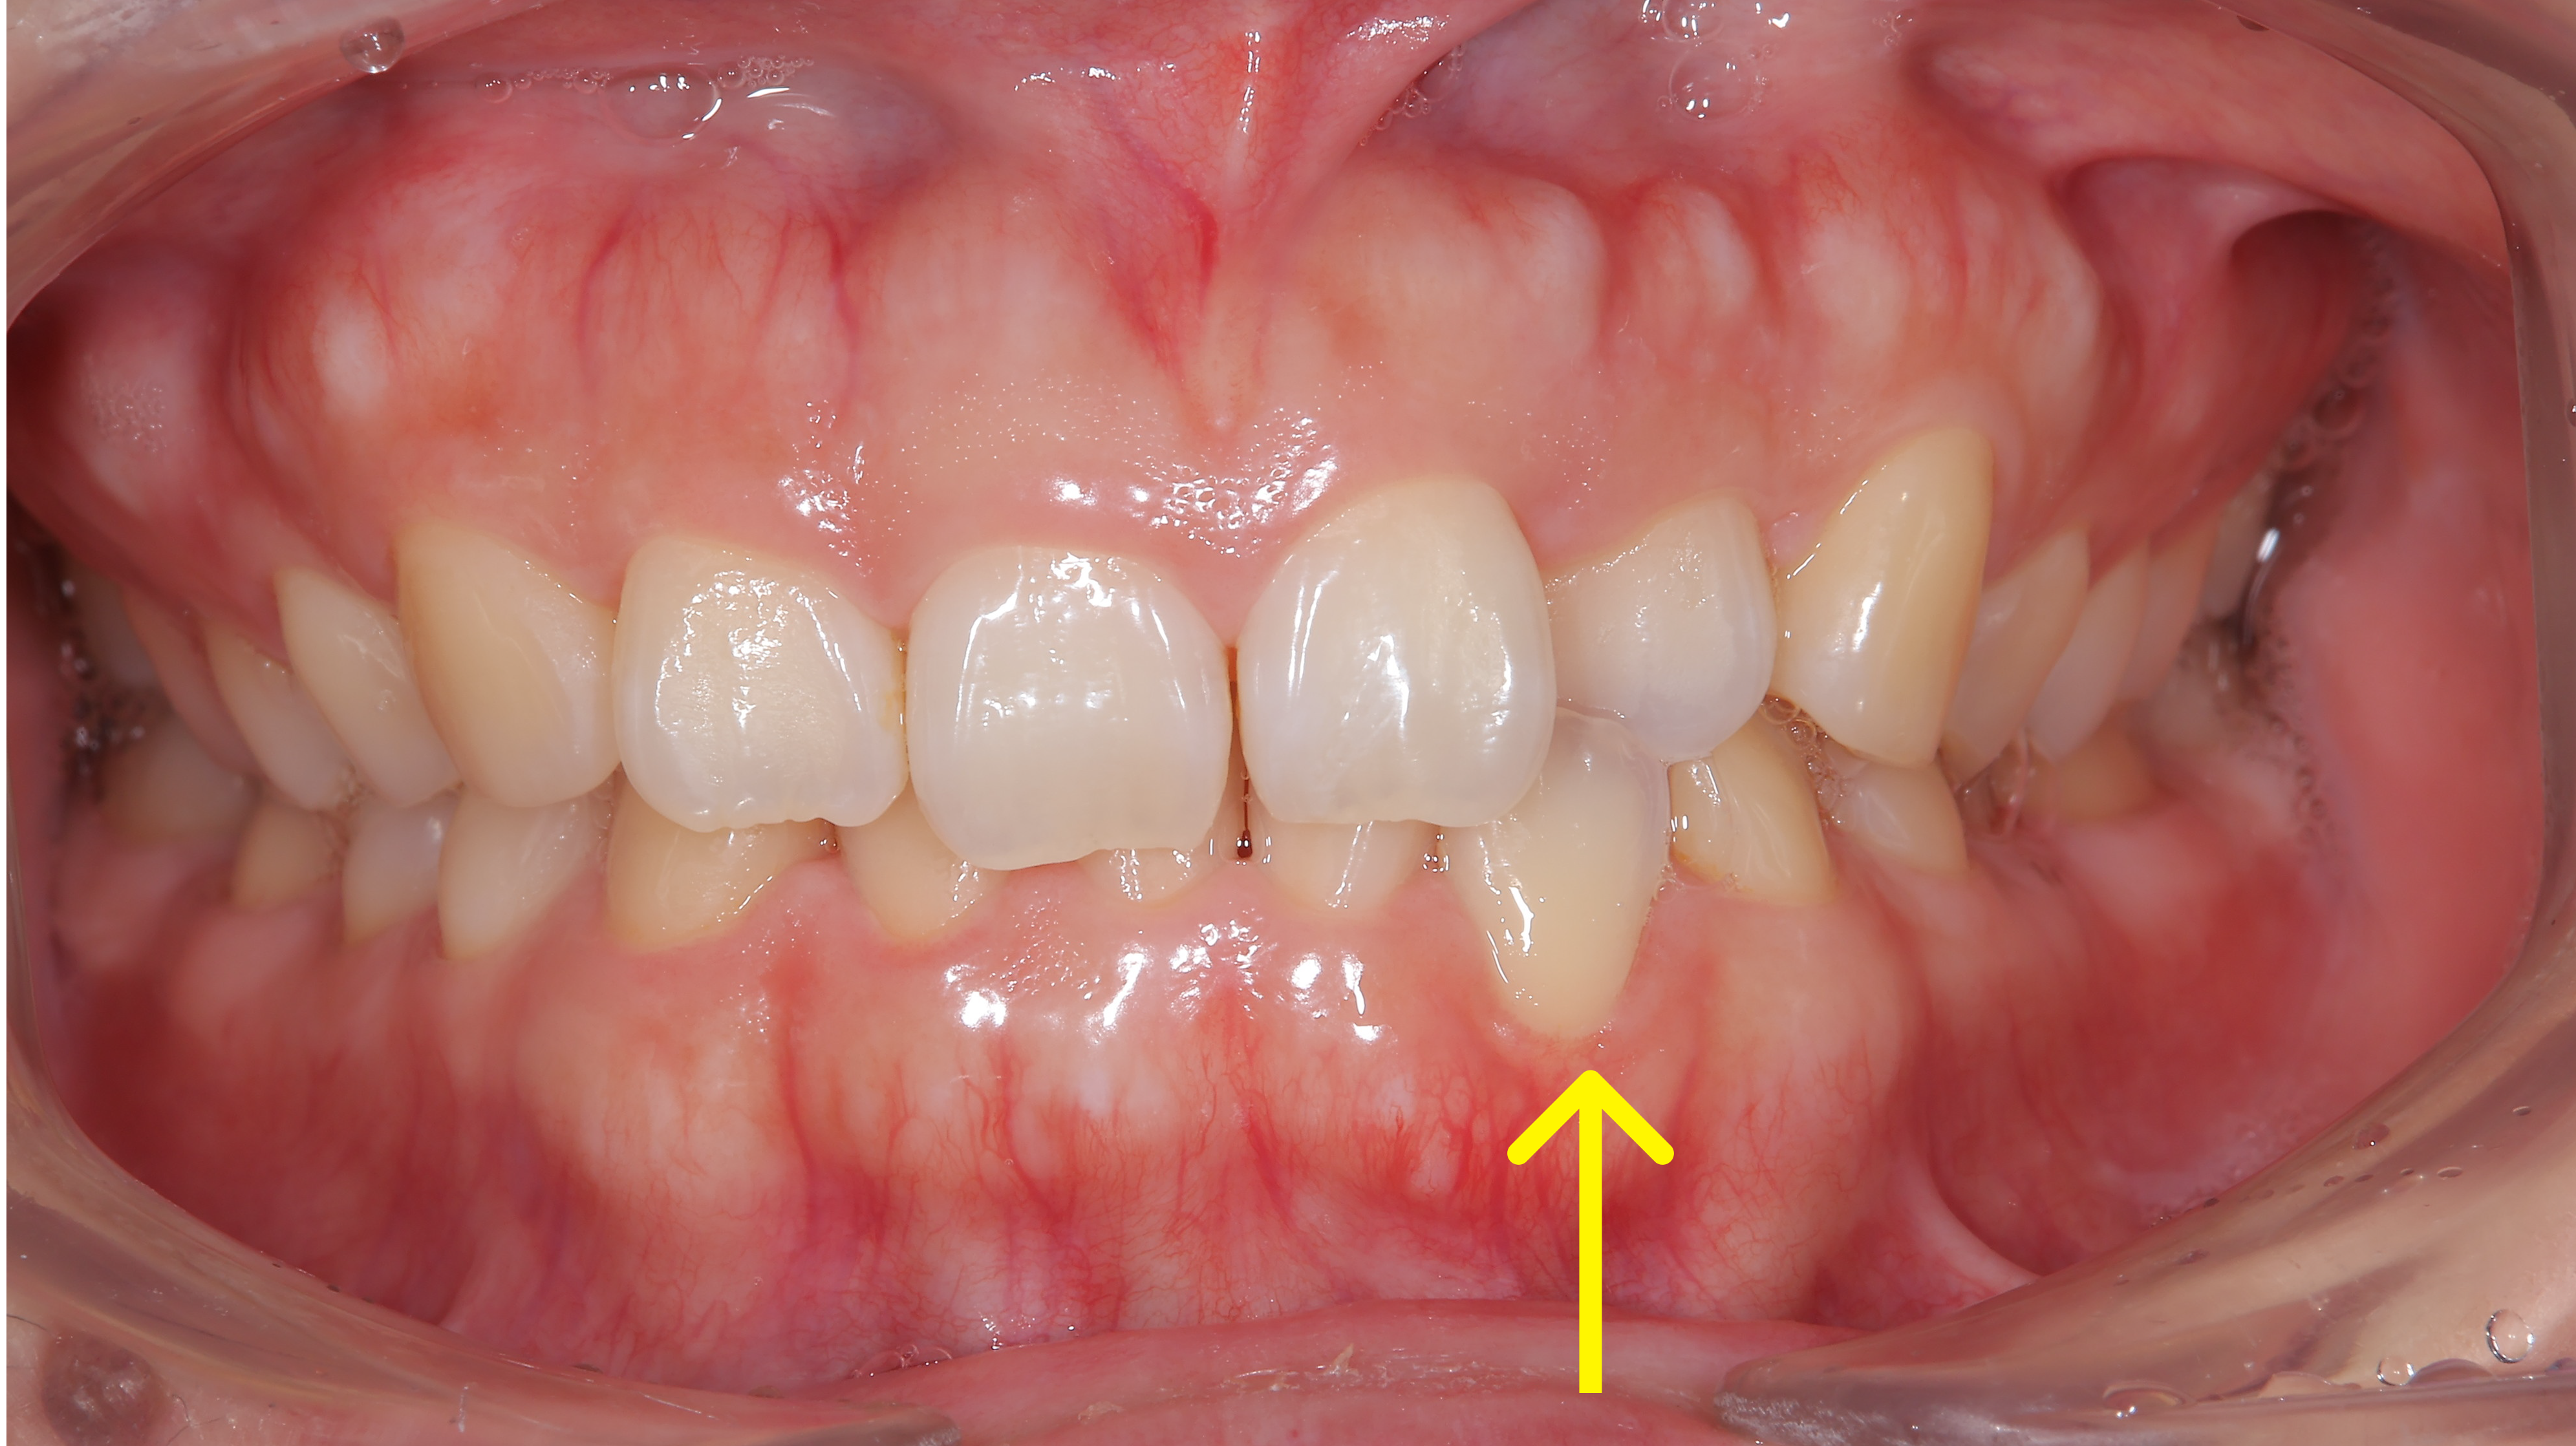

治療概要:矢印の歯は反対咬合(上の歯より下の歯の方が前に出ている)になっています。また、この方も過蓋咬合で下の前歯がほとんど見えません。

ほぼ他の歯が並んだ状態でも、やはりこの矢印の歯だけ動きが悪かったのと、左下の捻れた歯がなかなか治らなかったので、ワイヤーを部分的に使用させてもらいました。

下の写真が術前術後の比較です。下の前歯が見えるようになりました。上の前歯の傾きが変わるだけで口元の印象も変化します。